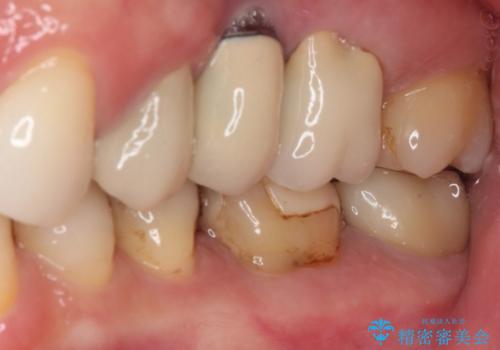

- 奥歯にものが挟まったり引っかかったりすることを気にして来院された患者様です。

詰め物と歯に隙間ができており、既に根管治療をされた歯であったため、フルジルコニアクラウンにて補綴治療をすることとしました。

咬んだときに違和感があるとのことだったので、根管治療を事前におこなうこととしました。